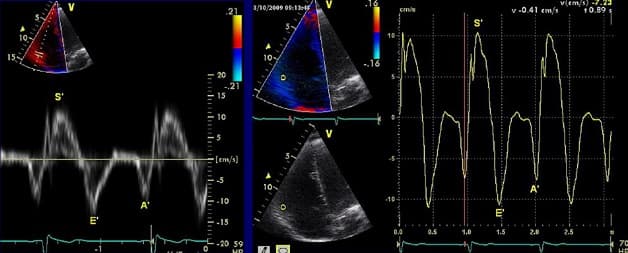

Siêu âm doppler tim là phương pháp giúp khảo sát sự biến đổi hình thái, chức năng và huyết động của tim thông qua hiệu ứng doppler, việc sử dụng doppler xung, doppler liên tục, doppler màu. Vậy khi nào cần siêu âm doppler tim?

Siêu âm Doppler là một phương pháp thăm dò chẩn đoán hình ảnh khảo sát vật thể chuyển động qua đầu dò phát – nhận sóng siêu âm. Với các tín hiệu tần số phát ra từ đầu dò của máy siêu âm và tần số nhận về khi khảo sát vật thể chuyển động, máy sẽ thực hiện thao tác tổng hợp và hiển thị trên màn hình dưới dạng hình ảnh có màu sắc, các dạng sóng phổ khác nhau hoặc các tín hiệu âm thanh có thể nghe được.

Bác sĩ có thể điều chỉnh đầu dò để có góc nhìn khác nhau và trực tiếp đánh giá được các thông số trên hình ảnh siêu âm. Bác sĩ cũng có thể chụp lại các hình ảnh bất thường để tiến hành hội chẩn với các chuyên gia tim mạch. Qua đó, đánh giá được chức năng tống máu của tim, bất thường của cơ tim và van tim,… Việc quan sát điện tâm đồ đồng thời với hình ảnh siêu âm doppler để giúp nhận biết được dòng máu đang ở thì tâm thu, tâm trương hay ở cả hai thì.